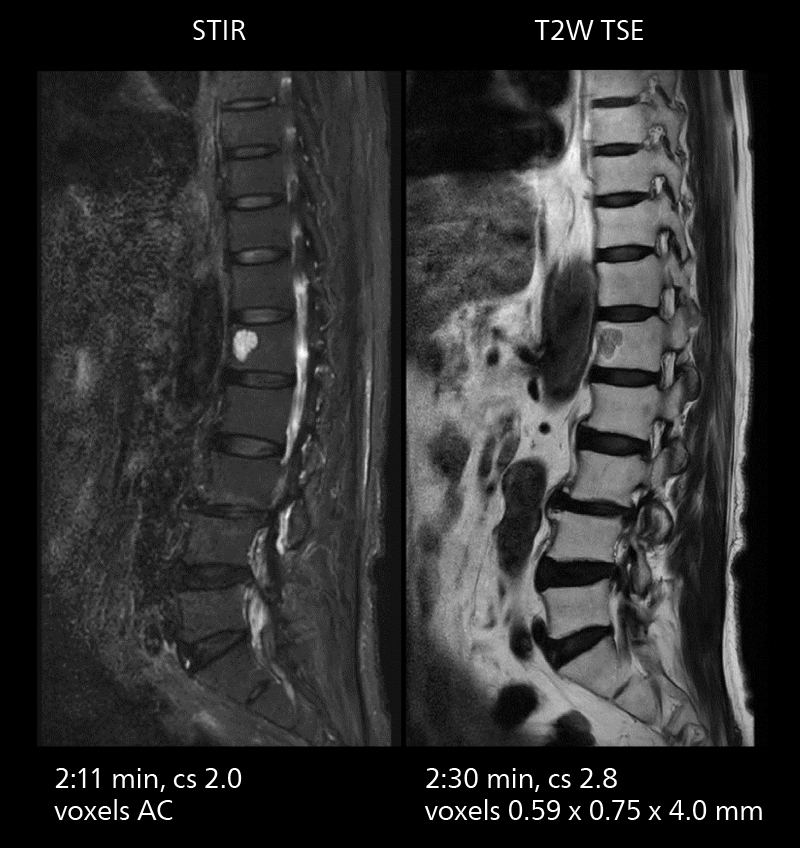

Lumbar spine MRI

Crisp images are obtained with high resolution and short scan times using Elition X. A cyst can be seen.